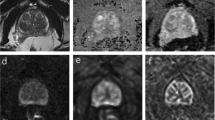

MR/3D-TRUS registration

The mean Dice score between the segmented lesions from the MRI and the 3D-TRUS was 0.67 of five registrations. The mean TRE between the registered MR and 3D TRUS images was \(2.52 \pm 0.65mm\). The mean of the Hausdorff distances between the segmented lesions amounted to 3.18 mm while the average of the mean boundary distance was 0.88 mm. Figure 8 shows an example of the image fusion between the MRI and the 3D-TRUS with the prostate phantom.

Coronal views of the prostate phantom images from the 3D-TRUS (a) and from the MR (b) and images from the axial (a), sagittal (b) and coronal (c) planes with the registered MRI and the 3D-TRUS images using the prostate phantom. From this registration the Dice score was calculated from the segmented lesion.